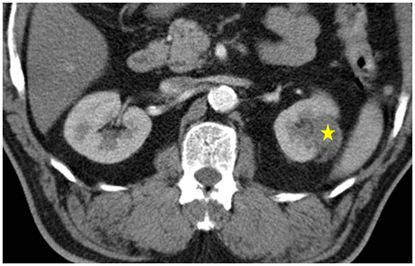

治療後三個月,以電腦斷層追蹤為主,有時會用超音波或磁振造影的方式追蹤。若有殘存或復發的腫瘤則可重複接受此方法治療。

原則上腫瘤小於4公分,此治療可達到完全根除的效果。若腫瘤太大,可以此治療部份消除,也可於施行多於一次的治療以達根除效果。